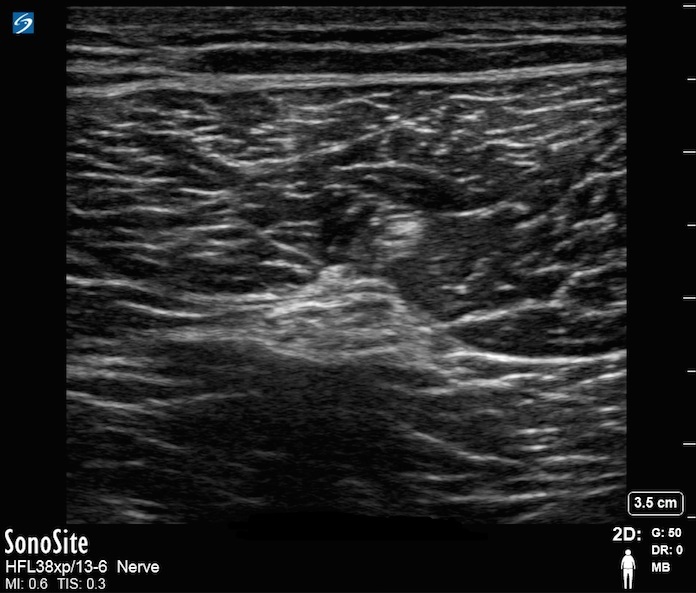

膝窩坐骨神経画像